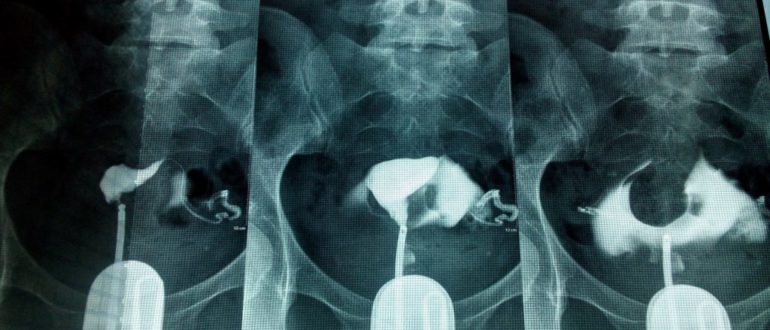

Проходимость маточных труб: как проверяют, какой метод наиболее достоверный, как лучше и где проверить, почему появились боли Проверяют проходимость маточных труб разными способами – гидросонография, метросальпингография, фертилоскопия, пертурбация,…